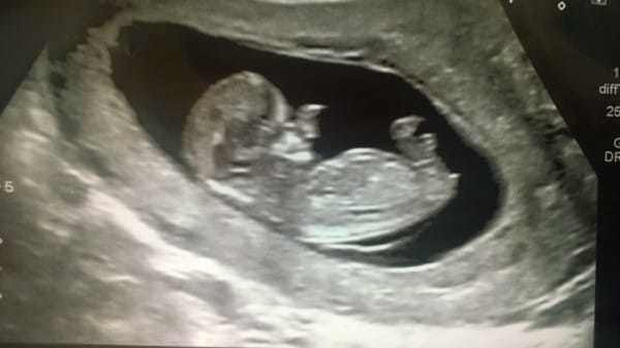

Năm đó, mẹ bé là Amy Poole nhận tin sốc khi mang thai lần hai. Ngay khi siêu âm, bác sĩ đã nhìn thấy điều gì đó bất thường trên khuôn mặt của cậu bé. Trong quá trình chụp cắt lớp xuyên suốt 20 tuần, bác sĩ thấy rằng con trai của Amy có mô mềm phát triển khó kiểm soát xung quanh vùng mũi. Amy biết rằng con trai mình sinh ra sẽ không giống những đứa trẻ bình thường khác, nhưng thực tế tàn khốc hơn rất nhiều so với những gì cô tưởng tượng.

Dị tật của Ollie đã được đoán trước phần nào qua siêu âm và chụp cắt lớp